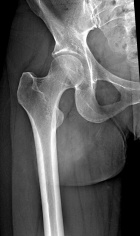

40 year old female presents with c/o burning/stabbing pain in her R anterolateral thigh. Pain has been present intermittently for >15 yrs, but has recently increased in intensity and frequency.

Zoom image: Radiological image Radiological image.